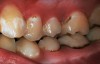

The authors' protocol for insertion of SDF-coated soft dental picks involves isolating the teeth with cotton rolls or other means, flossing the interproximal site to clear food debris and dental plaque, and then inserting a SDF-coated pick (Figure 1 and Figure 2) to saturate the contacting surfaces of the teeth with the fluid. This treatment is painless and requires no anesthetic. The pick should remain in place for at least 60 seconds and can be gently pulled in and out to agitate the fluid for enhanced surface coverage by capillary action. Additional SDF can be wiped on, using a small applicator, above the contact and in the buccal and lingual sluiceways. Excess fluid and any blood elicited may be blotted with a cotton swab. An additional 60-second insertion may be applied in the same way if there is radiographic evidence of a deeper decalcification or caries lesion. With the pick still in place, 5% (or 2.5%) fluoride varnish is painted over the treatment area, and the pick is then withdrawn.

Interproximal insertion of SDF is demonstrated in different patients in Figure 3 through Figure 11. Various diameters and brands of soft dental picks may be used depending on the closeness of the proximal surfaces and ease of insertion; for example, some picks are designed for use in wider spaces between teeth. This protocol also offers versatility. Figure 3, for example, shows the simultaneous use of three thin soft dental picks to saturate proximal surfaces with SDF in a teenaged patient; the treated regions were subsequently covered with fluoride varnish (Figure 4). This patient was initially treated in April 2019 (Figure 5), with an identical re-application 3 months later. As shown in Figure 6, the December 2019 bitewing film revealed good results with the possible exception of the contact regions of the maxillary first and second molars. New SDF application was completed in the December appointment.

Fig 4. Three thin soft dental picks were used simultaneously for SDF proximal surface saturations in a teenaged patient (Fig 3). After 60 seconds, the treated regions were covered with 5% fluoride varnish (Fig 4). A comparison can be seen of pre-SDF-treatment bitewing films (Fig 5) and 8-month post-SDF bitewing films (Fig 6) for the patient shown in Fig 3 and Fig 4. Radiolucencies were similar or improved, except for contact of maxillary first and second molars.

Figure 4